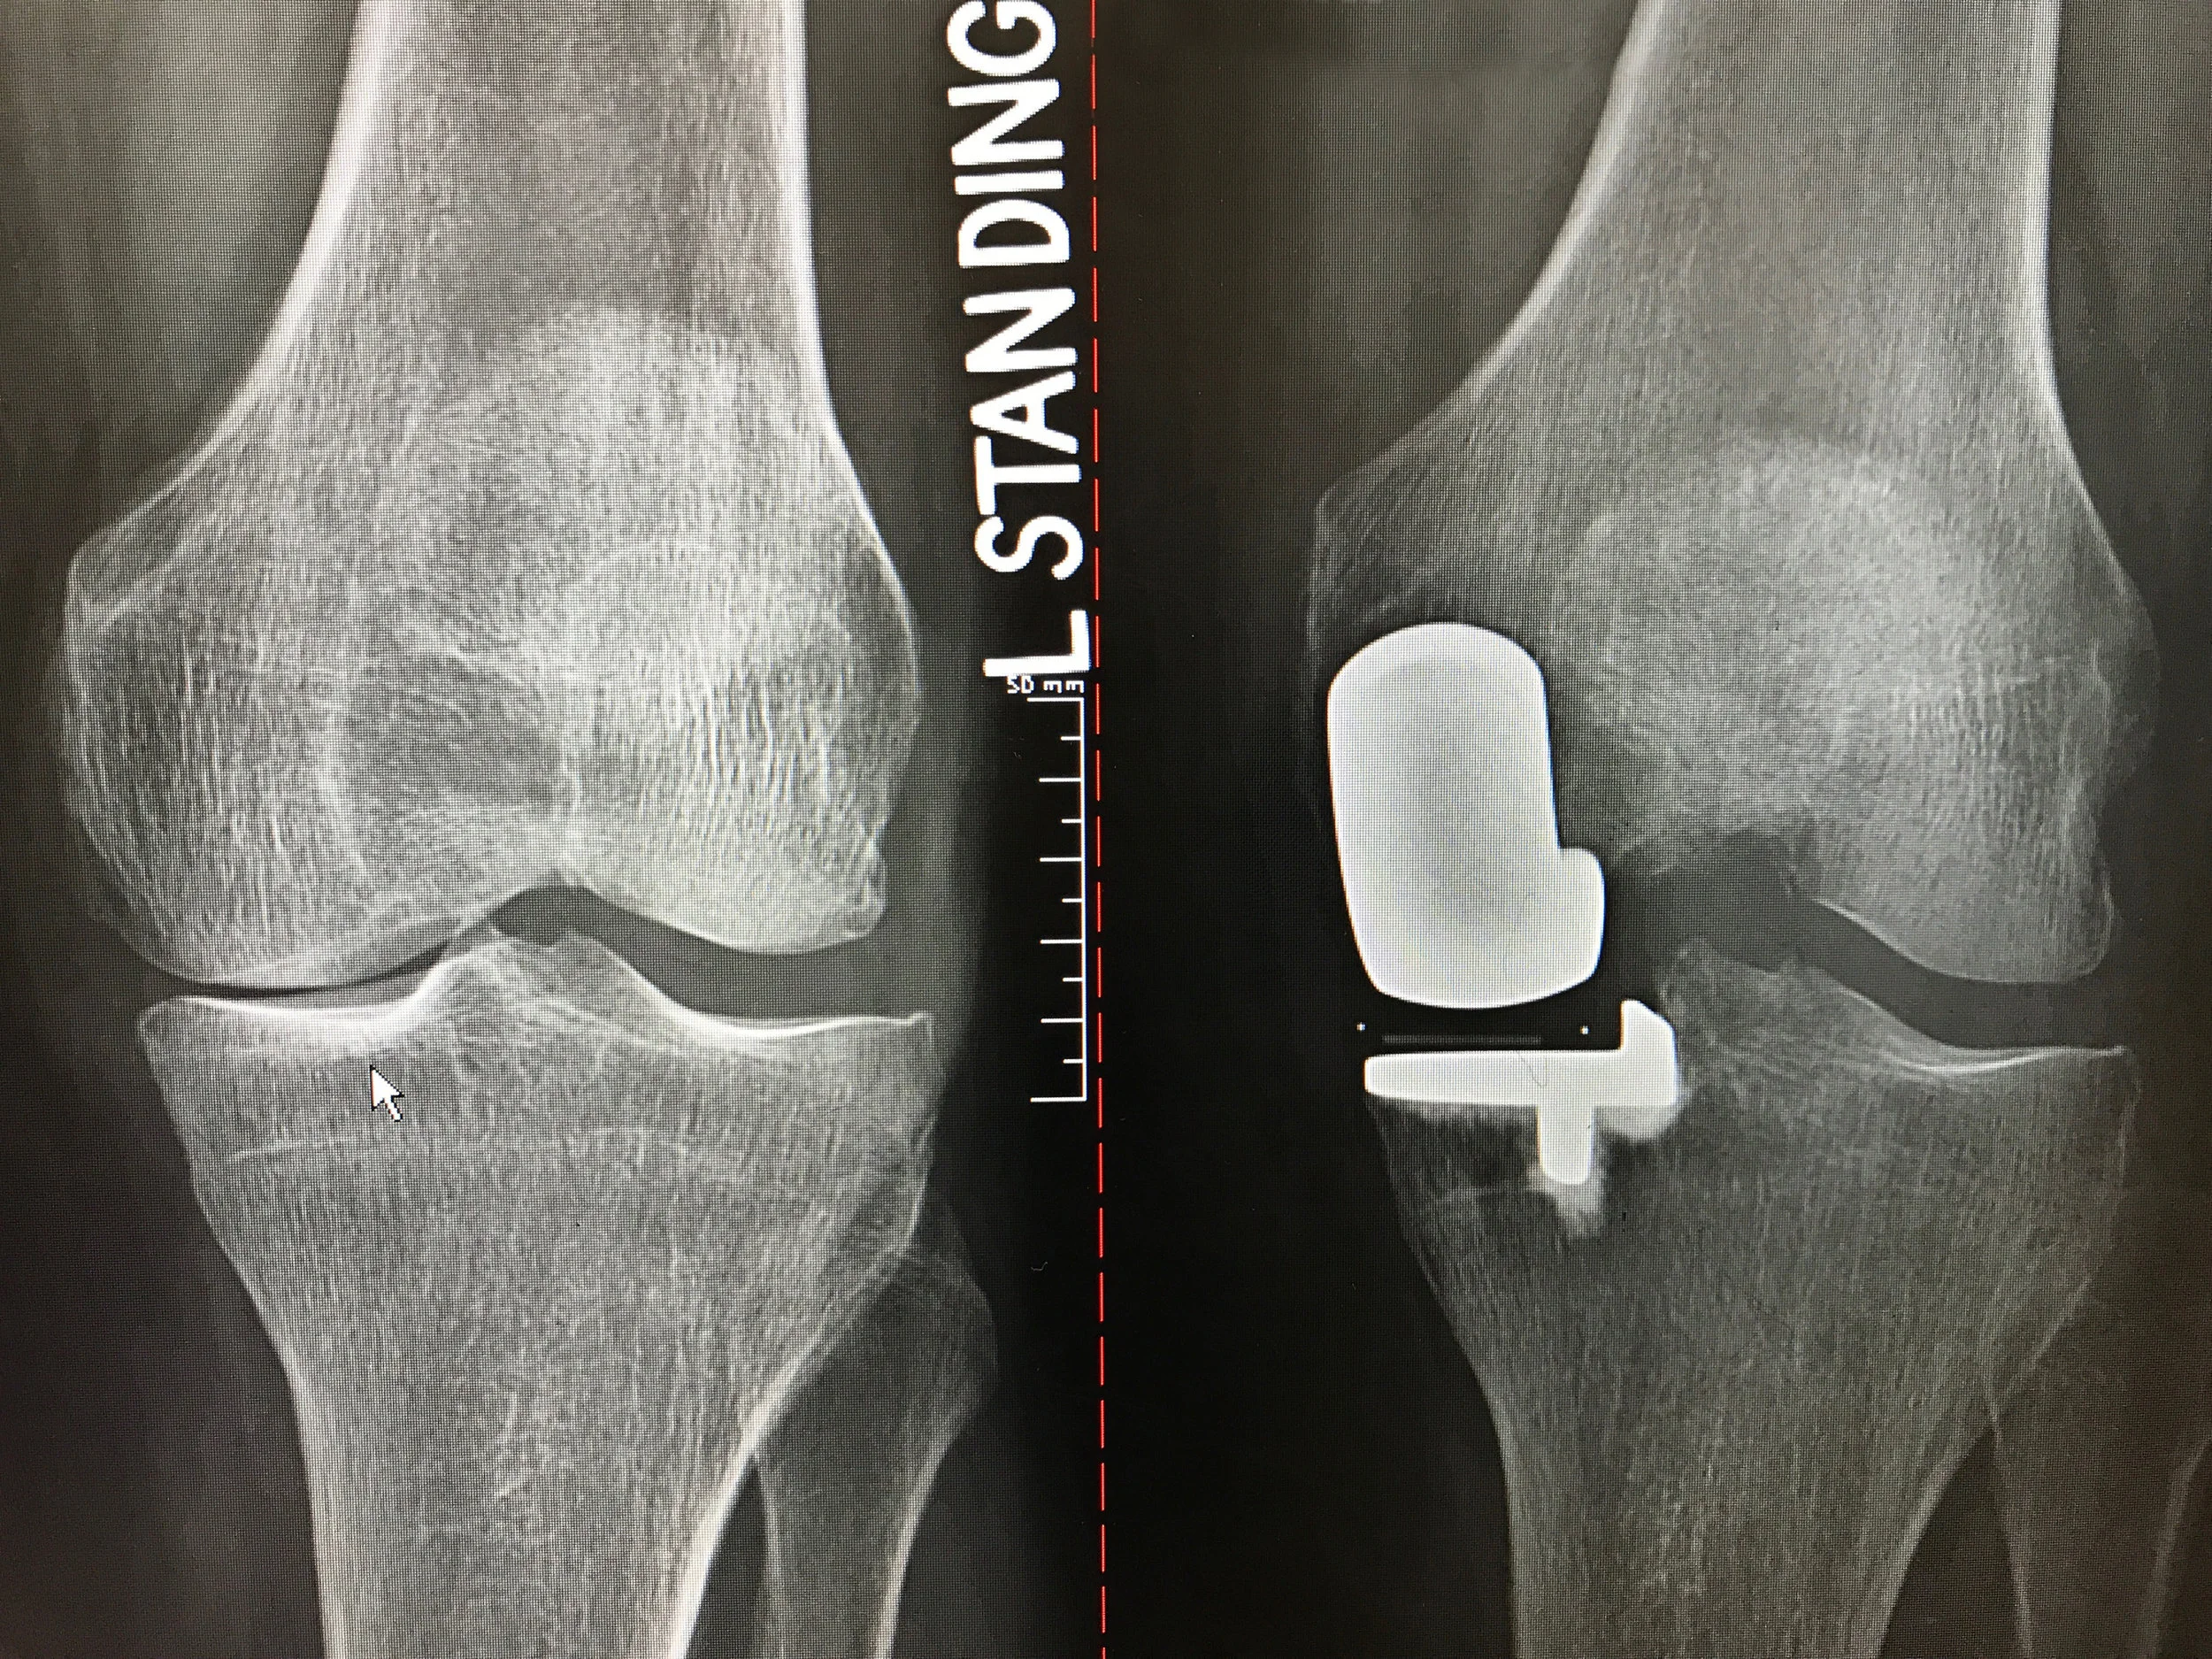

Before: Bone on bone arthritis affecting only the medial (inside) compartment

After: Partial Knee Replacement

BIOMET OXFORD PKR